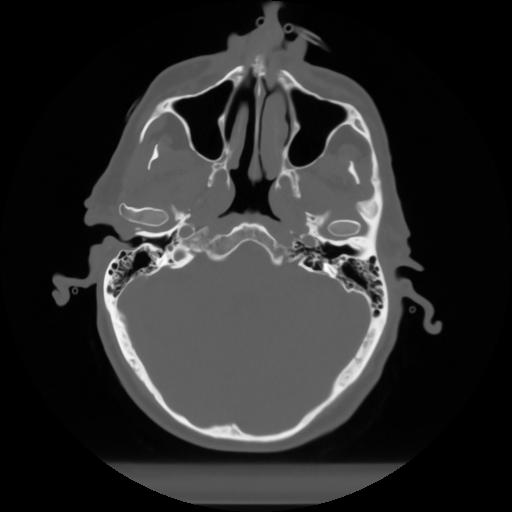

10 P.BLANDAS,,Axial,2.0,P.BLANDAS,,